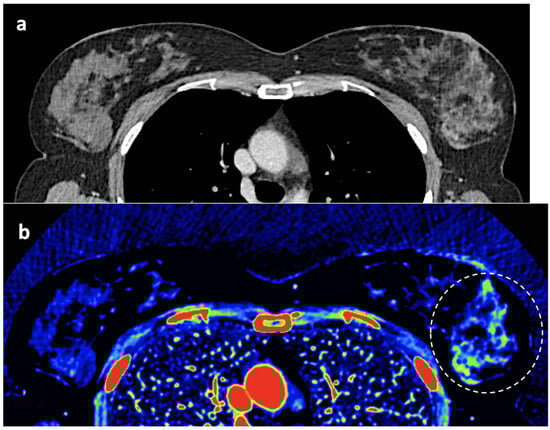

Figure 11. Adrenal adenoma. Fat fraction of adrenal lesions evaluated with DECT may be an alternative diagnostic tool to VUE attenuation using the traditional threshold of 10 HU or lower in the assessment of adrenal adenomas. Fat quantification DECT image evidences bilateral lipid-rich adrenal adenomas with increased fat fraction. - Breast imaging. DECT seems to be a reliable tool for diagnosis and locoregional staging of breast cancer [36,37,38,39,40] (Figure 12). Klein et al. [37] found robust cut-off points for the differentiation of benign and malignant lesions (Zeff < 7.7, iodine content of <0.8 mg/mL). The DECT quantitative parameters may also be useful in predicting breast cancer invasiveness and histopathological and molecular subtypes of breast tumors. In the case of node staging, the similarity of quantitative DECT parameters between the primary lesion and axillary LNs may predict axillary metastasis in breast cancer [40,41].

Figure 12. Breast 120 kVp-like (a) and color-coded iodine map (b) images. Breast lesion detection. Multicentric left breast invasive ductal carcinoma can easily be detected based on iodine uptake (dotted circle) compared to the 120 kVp-like image, where the diagnosis is challenging. - Currently, there is not a widely reported use of DECT in clinical management of prostate cancer. However, DECT imaging may facilitate the depiction of focal areas of increased enhancement in the periphery of the prostate in contrast-enhanced CT that may represent a clinically significant cancer and deserve further workup [42] (Figure 13).